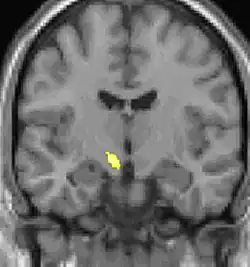

| Positron emission tomography (PET) shows brain areas being activated during pain. | ||

| Voxel-based morphometry shows brain area structural differences. | ||

Positron emission tomography (PET) scans indicate the brain areas which are activated during attack only, compared to pain free periods. These pictures show brain areas that are active during pain in yellow/orange color (called "pain matrix"). The area in the center (in all three views) is activated only during cluster headaches. The bottom row voxel-based morphometry shows structural brain differences between individuals with and without CH; only a portion of the hypothalamus is different.[37]